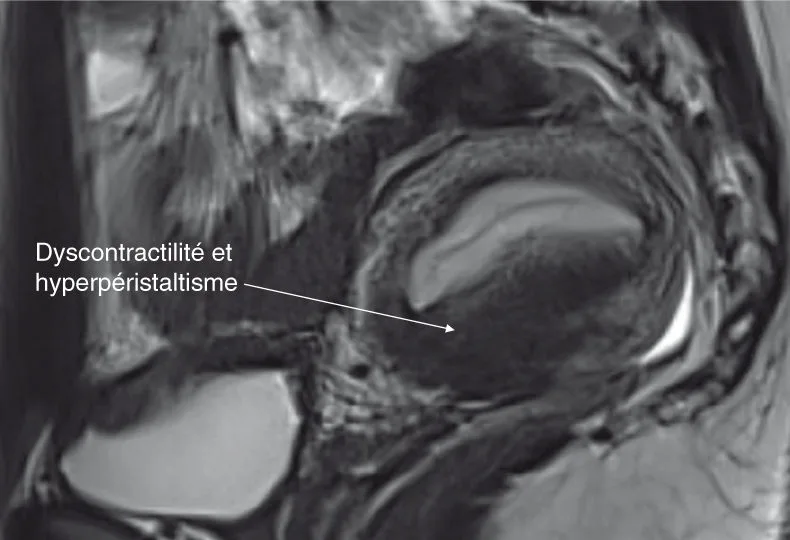

indirects : troubles de la contraction du myomètre externe (néomètre) et/ou hyperpéristaltisme du myomètre interne (archimyomètre) simulant alors une hypertrophie de la zone jonctionnelle, mais disparaissant sur la deuxième séquence d'étude sagittale de l'utérus pratiquée en fin d'examen, permettant ainsi d'objectiver cette dyscontractilité à ne pas confondre avec une hypertrophie de la zone jonctionnelle (figure 6.3).

Figure 6.3. Dix-sept ans, dysménorrhée avec AS, ménorragies. Premier T2 sagittal, coupes de 3 mm. Source : Dr Petit.